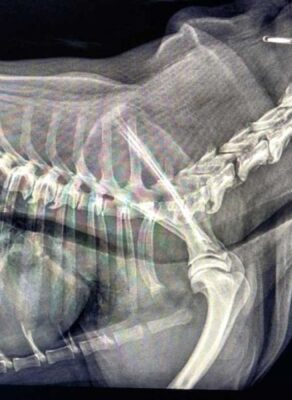

Zapadanie tchawicy u psów (TCS-Tracheal Collapse Syndrome)

Źródło: https://wetgliwice.pl/ Zapadanie tchawicy u psów (TCS-Tracheal Collapse Syndrome) Zapadanie tchawicy u psów (TCS-Tracheal Collapse Syndrome) jest przewlekłą chorobą …